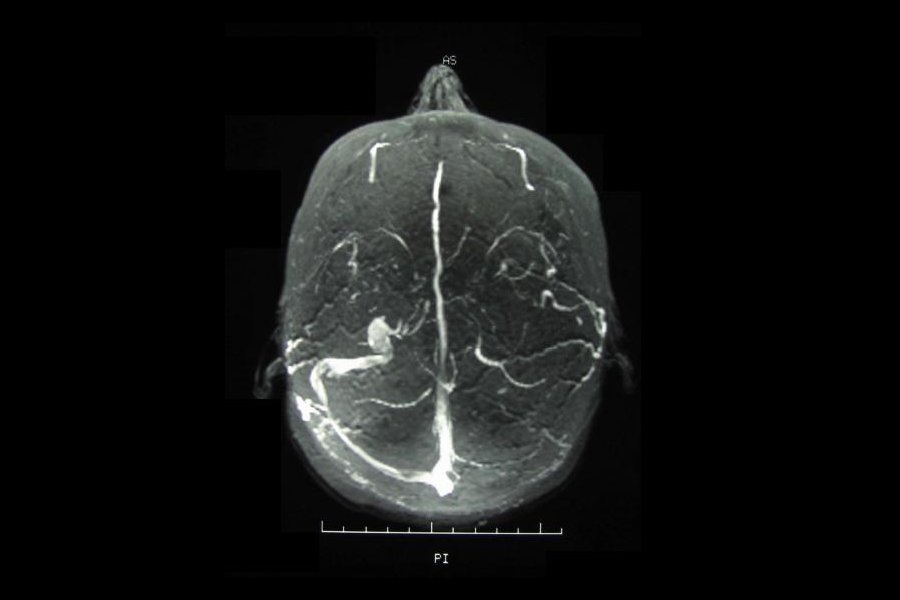

Behcetova choroba je autoimunitní onemocnění, při kterém krevní cévy postihne chronický zánět. V ústech a na genitáliích zanechává vřídky a může zasáhnout i oči, ledviny nebo nervový systém. Své jméno dostala po tureckém lékaři, který ji popsal v roce 1937. V Evropě je choroba vzácná, ale čím dále na východ, tím se s ní lékaři setkávají častěji. Výskyt Behcetovy choroby v podstatě kopíruje hedvábnou stezku, po které kdysi zboží z Dálného východu putovalo do Evropy.

Obchod mnohdy provázela i výměna genetické informace mezi obchodníky a místními lidmi a spolu s ní se podél hedvábné stezky šířila i náchylnost k onemocnění. Geny, které jsou za Behcetovu chorobu zodpovědné, se teď poprvé podařilo identifikovat britským vědcům. V Turecku nemoc postihuje čtyři lidi z tisíce, což vědcům umožnilo provést rozsáhlou genetickou studii. Během ní vyšetřili téměř 2500 lidí a data srovnali s dalšími 5000 lidmi ze Středního východu, Evropy i Asie. Zjistili, že za zvýšeným rizikem rozvoje Behcetovy choroby stojí trojice genů (HLA-B51, IL10, IL23R-IL12RB2), které kódují různé složky imunitního systému. Objev může vydláždit cestu k lepšímu poznání patologie Behcetovy choroby a snad i novému typu léčby.